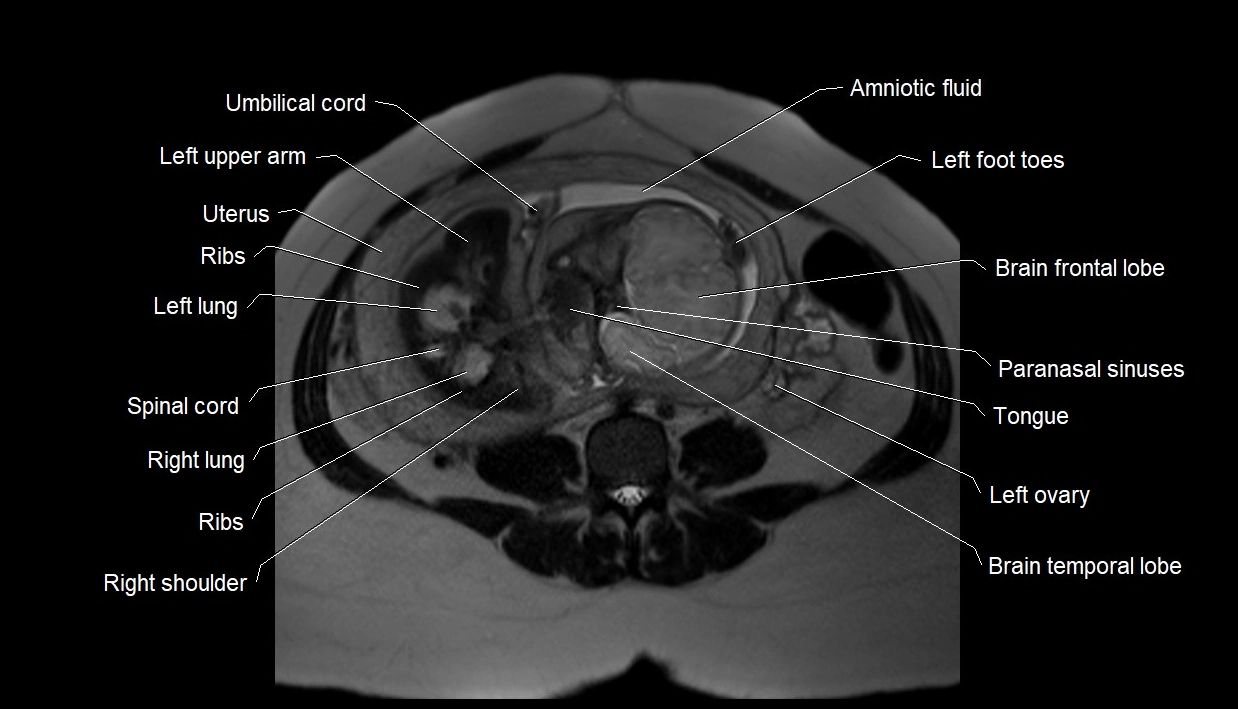

MRI Appearance

T2 HASTE (T2 GRE):

• Amniotic fluid shows very bright hyperintense signal

• Provides natural contrast against fetus and placenta

• Small particles (vernix) may appear as scattered hypointense foci within bright fluid

T1 GRE:

• Amniotic fluid shows low signal intensity (dark)

• Hemorrhage, infection, or proteinaceous content may cause focal or diffuse high signal intensity